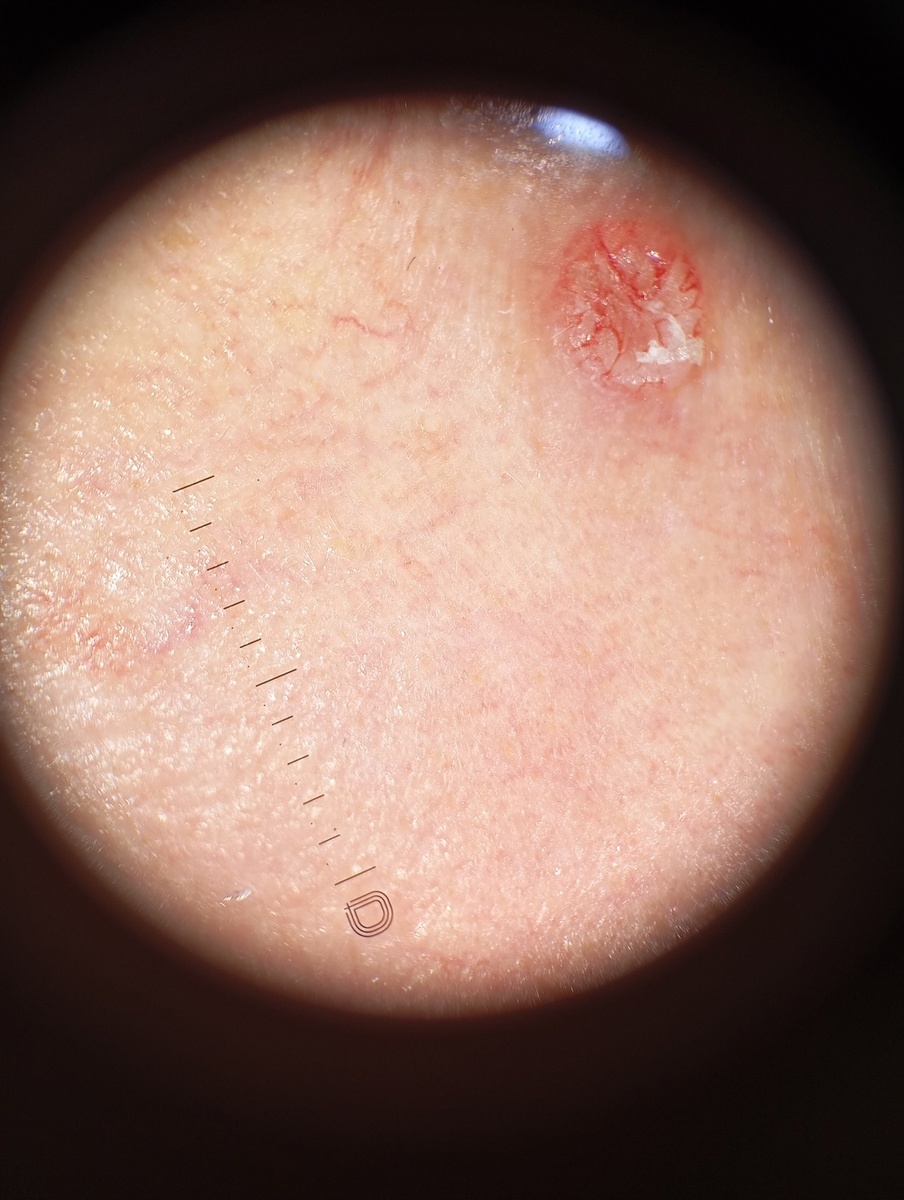

Недавний клинический случай ещё раз напоминает: с кожей не шутят. Ко мне направили мужчину 41 года после консультации дерматолога. Поводом стало небольшое образование на коже — сам пациент описал его как «болячку» диаметром около 3 мм. Оно было незаметным и не причиняло боли, но вызвало вопросы.

После осмотра и дерматоскопии у меня также возникли серьёзные подозрения. Для уточнения диагноза провели панч-биопсию — минимально инвазивную процедуру для взятия ткани на исследование. Результаты подтвердили предположения: базально-клеточный рак кожи.

Это самый распространённый тип рака кожи, который редко даёт метастазы, но при отсутствии лечения может разрушать ткани и оставлять серьёзные косметические дефекты.